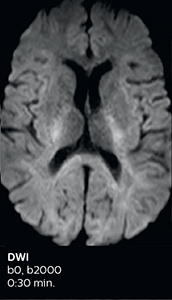

Fast MS protocol with optional sequences

The abbreviated MS protocol for brain is only around 9 minutes, so in case of suspected multiple sclerosis, one or two more advanced sequences may be added, such as PSIR (phase sensitive inversion recovery) or susceptibility-weighted sequences to help us make more confident diagnoses in these inflammatory cases.

In this example, the optional 3D multishot susceptibility weighted sequence with 0.6 mm isotropic voxels is 2 lesions with a central vein sign (arrows) and one lesion with a phase-rim sign (arrowhead). The total scan time, including SmartBrain and axial PD/T2 3mm, is 11:10 min. and is 18:30 min. with the optional 3D PSIR and 3D SWI multishot included.